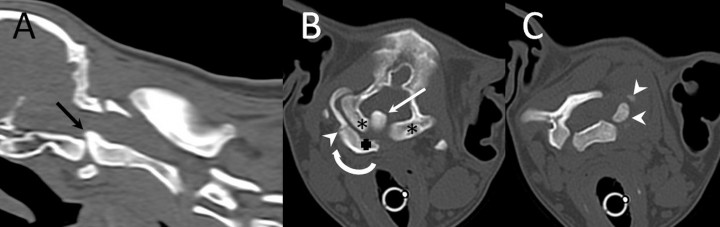

Es referida para evaluación neurológica una perra mestiza de 4 meses de edad y 23 kilos de peso por presentar dolor cervical y tetraparesia de 4 días de evolución tras sufrir un traumatismo. En la exploración física se palpó una asimetría del atlas, que parecía rotado, lo que hacía que el paciente sufriese una desviación severa del cuello con gran dolor a la manipulación. El examen neurológico reveló tetraparesia ambulatoria severa con retraso simétrico de las reacciones posturales en las cuatro extremidades. Los reflejos medulares y la evaluación de los pares craneales eran normales. Este examen fue compatible con una afección focal o difusa de los segmentos medulares C1 - C5. El diagnóstico diferencial, teniendo en cuenta la historia clínica y la exploración física, incluyó principalmente procesos de carácter malformativo, sin poder descartarse enfermedades traumáticas, inflamatorias o neoplásicas. Se realizaron radiografías de la columna cervical en proyección lateral y ventrodorsal donde se apreció una inestabilidad de la articulación AA evidenciada por aumento de distancia entre la lámina del atlas y la apófisis espinosa del axis (Fig. 1A). Sin embargo, el hallazgo más relevante consistió en la ausencia del ala (apófisis transversa modificada) y la mitad izquierda del cuerpo del atlas (Fig. 1B). Posteriormente se procedió a la realización de una tomografía computarizada (TC) donde se confirmó la existencia de una malformación cervical con desplazamiento rostral del axis, que hacía que el diente del axis sobrepasase el límite craneal del cuerpo del atlas y los cóndilos del occipital, quedando en contacto con el aspecto ventral de la médula oblonga (signo radiológico denominado “invaginación basilar” en medicina humana) (Fig. 2, A y B). El atlas presentaba una agenesia de su mitad izquierda y en su lugar se apreciaron dos pequeños núcleos óseos independientes que ocupaban una posición dorsolateral izquierda no unidos con el resto de estructuras óseas (Fig. 2, C). Aunque el arco derecho del atlas quedaba íntimamente asociado con el cóndilo derecho del occipital, se evidenció una conformación atlanto-occipital derecha normal, con una línea articular bien formada pero rotada (Fig. 2, B). En el aspecto ventral del atlas se observaba el “intercentrum” 1, así como la sincondrosis neurocentral derecha (Fig. 2, B). Sin embargo, la sincondrosis neurocentral izquierda y la dorsal no podían ser evidenciadas debido a la ausencia del centro de osificación del arco neural izquierdo (Fig. 2, C). Todas estas alteraciones hacían que la articulación atlanto-occipital quedase rotada, haciendo que la cabeza girase en contra del sentido de las agujas del reloj visto desde un plano dorsal (Fig. 3, A y B). El agujero vertebral lateral y el agujero transverso del arco derecho del atlas estaban correctamente formados (Fig. 3, A). Por otro lado, se apreció como el aspecto craneal del cuerpo del axis y la apófisis odontoides estaban deformados, engrosados e hiperostóticos (Fig. 2, A). El borde craneal de la apófisis espinosa del axis quedaba deformado con desviación derecha, haciendo leve prominencia sobre el atlas (Figs. 2A y 3A). Posteriormente, se decidió realizar una resonancia magnética de la columna cervical para valorar el parénquima medular, donde se evidenció una severa compresión dorsoventral de la médula espinal a nivel de la articulación AA con obliteración del espacio subaracnoideo ventral y dorsal (Fig. 4). Las secuencias ponderadas en T2 demostraron la hiperintensidad del parénquima medular en el punto de mayor compromiso (Fig. 4).

<p><strong>(A) </strong>Reconstrucción sagital obtenida mediante TC de la unión craneocervical. Obsérvese el desplazamiento craneal del axis sobre el cuerpo del atlas que hace que el diente deformado y engrosado sobrepase el hueso basioccipital desplazando a la médula oblonga (flecha), denominado invaginación basilar. <strong>(B)</strong> Imagen transversal obtenida mediante TC a nivel de los cóndilos del occipital en la que se puede apreciar como el diente del axis está incluido dentro de la cavidad craneal (flecha) y la adecuada formación de los cóndilos del occipital (asteriscos). Tambien puede apreciarse el intercentrum I (cruz) y la sincondrosis neurocentral derecha (punta de flecha), pero no la izquierda. En esta imagen la rotación del atlas es evidente teniendo en cuenta la posición del cuerpo (flecha circular que indica el sentido de la rotación). <strong>(C) </strong>Imagen transversal obtenida mediante TC a nivel de la lámina del atlas en la que se aprecian dos núcleos de osificación independientes de posición dorsolateral izquierda (puntas de flecha).</p>

Figura 2

(A) Reconstrucción sagital obtenida mediante TC de la unión craneocervical. Obsérvese el desplazamiento craneal del axis sobre el cuerpo del atlas que hace que el diente deformado y engrosado sobrepase el hueso basioccipital desplazando a la médula oblonga (flecha), denominado invaginación basilar. (B) Imagen transversal obtenida mediante TC a nivel de los cóndilos del occipital en la que se puede apreciar como el diente del axis está incluido dentro de la cavidad craneal (flecha) y la adecuada formación de los cóndilos del occipital (asteriscos). Tambien puede apreciarse el intercentrum I (cruz) y la sincondrosis neurocentral derecha (punta de flecha), pero no la izquierda. En esta imagen la rotación del atlas es evidente teniendo en cuenta la posición del cuerpo (flecha circular que indica el sentido de la rotación). (C) Imagen transversal obtenida mediante TC a nivel de la lámina del atlas en la que se aprecian dos núcleos de osificación independientes de posición dorsolateral izquierda (puntas de flecha).